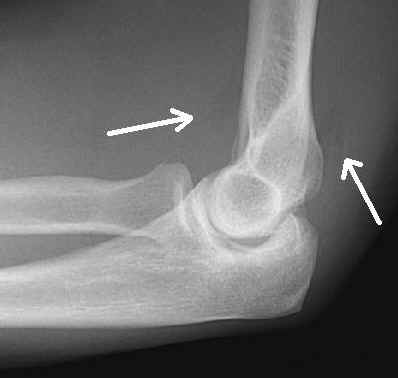

This lateral radiograph of the elbow demonstrates the presence of displaced anterior and posterior fat pads. This is abnormal and due to an undisplaced radial head fracture. There is no evidence of lipohemarthrosis.